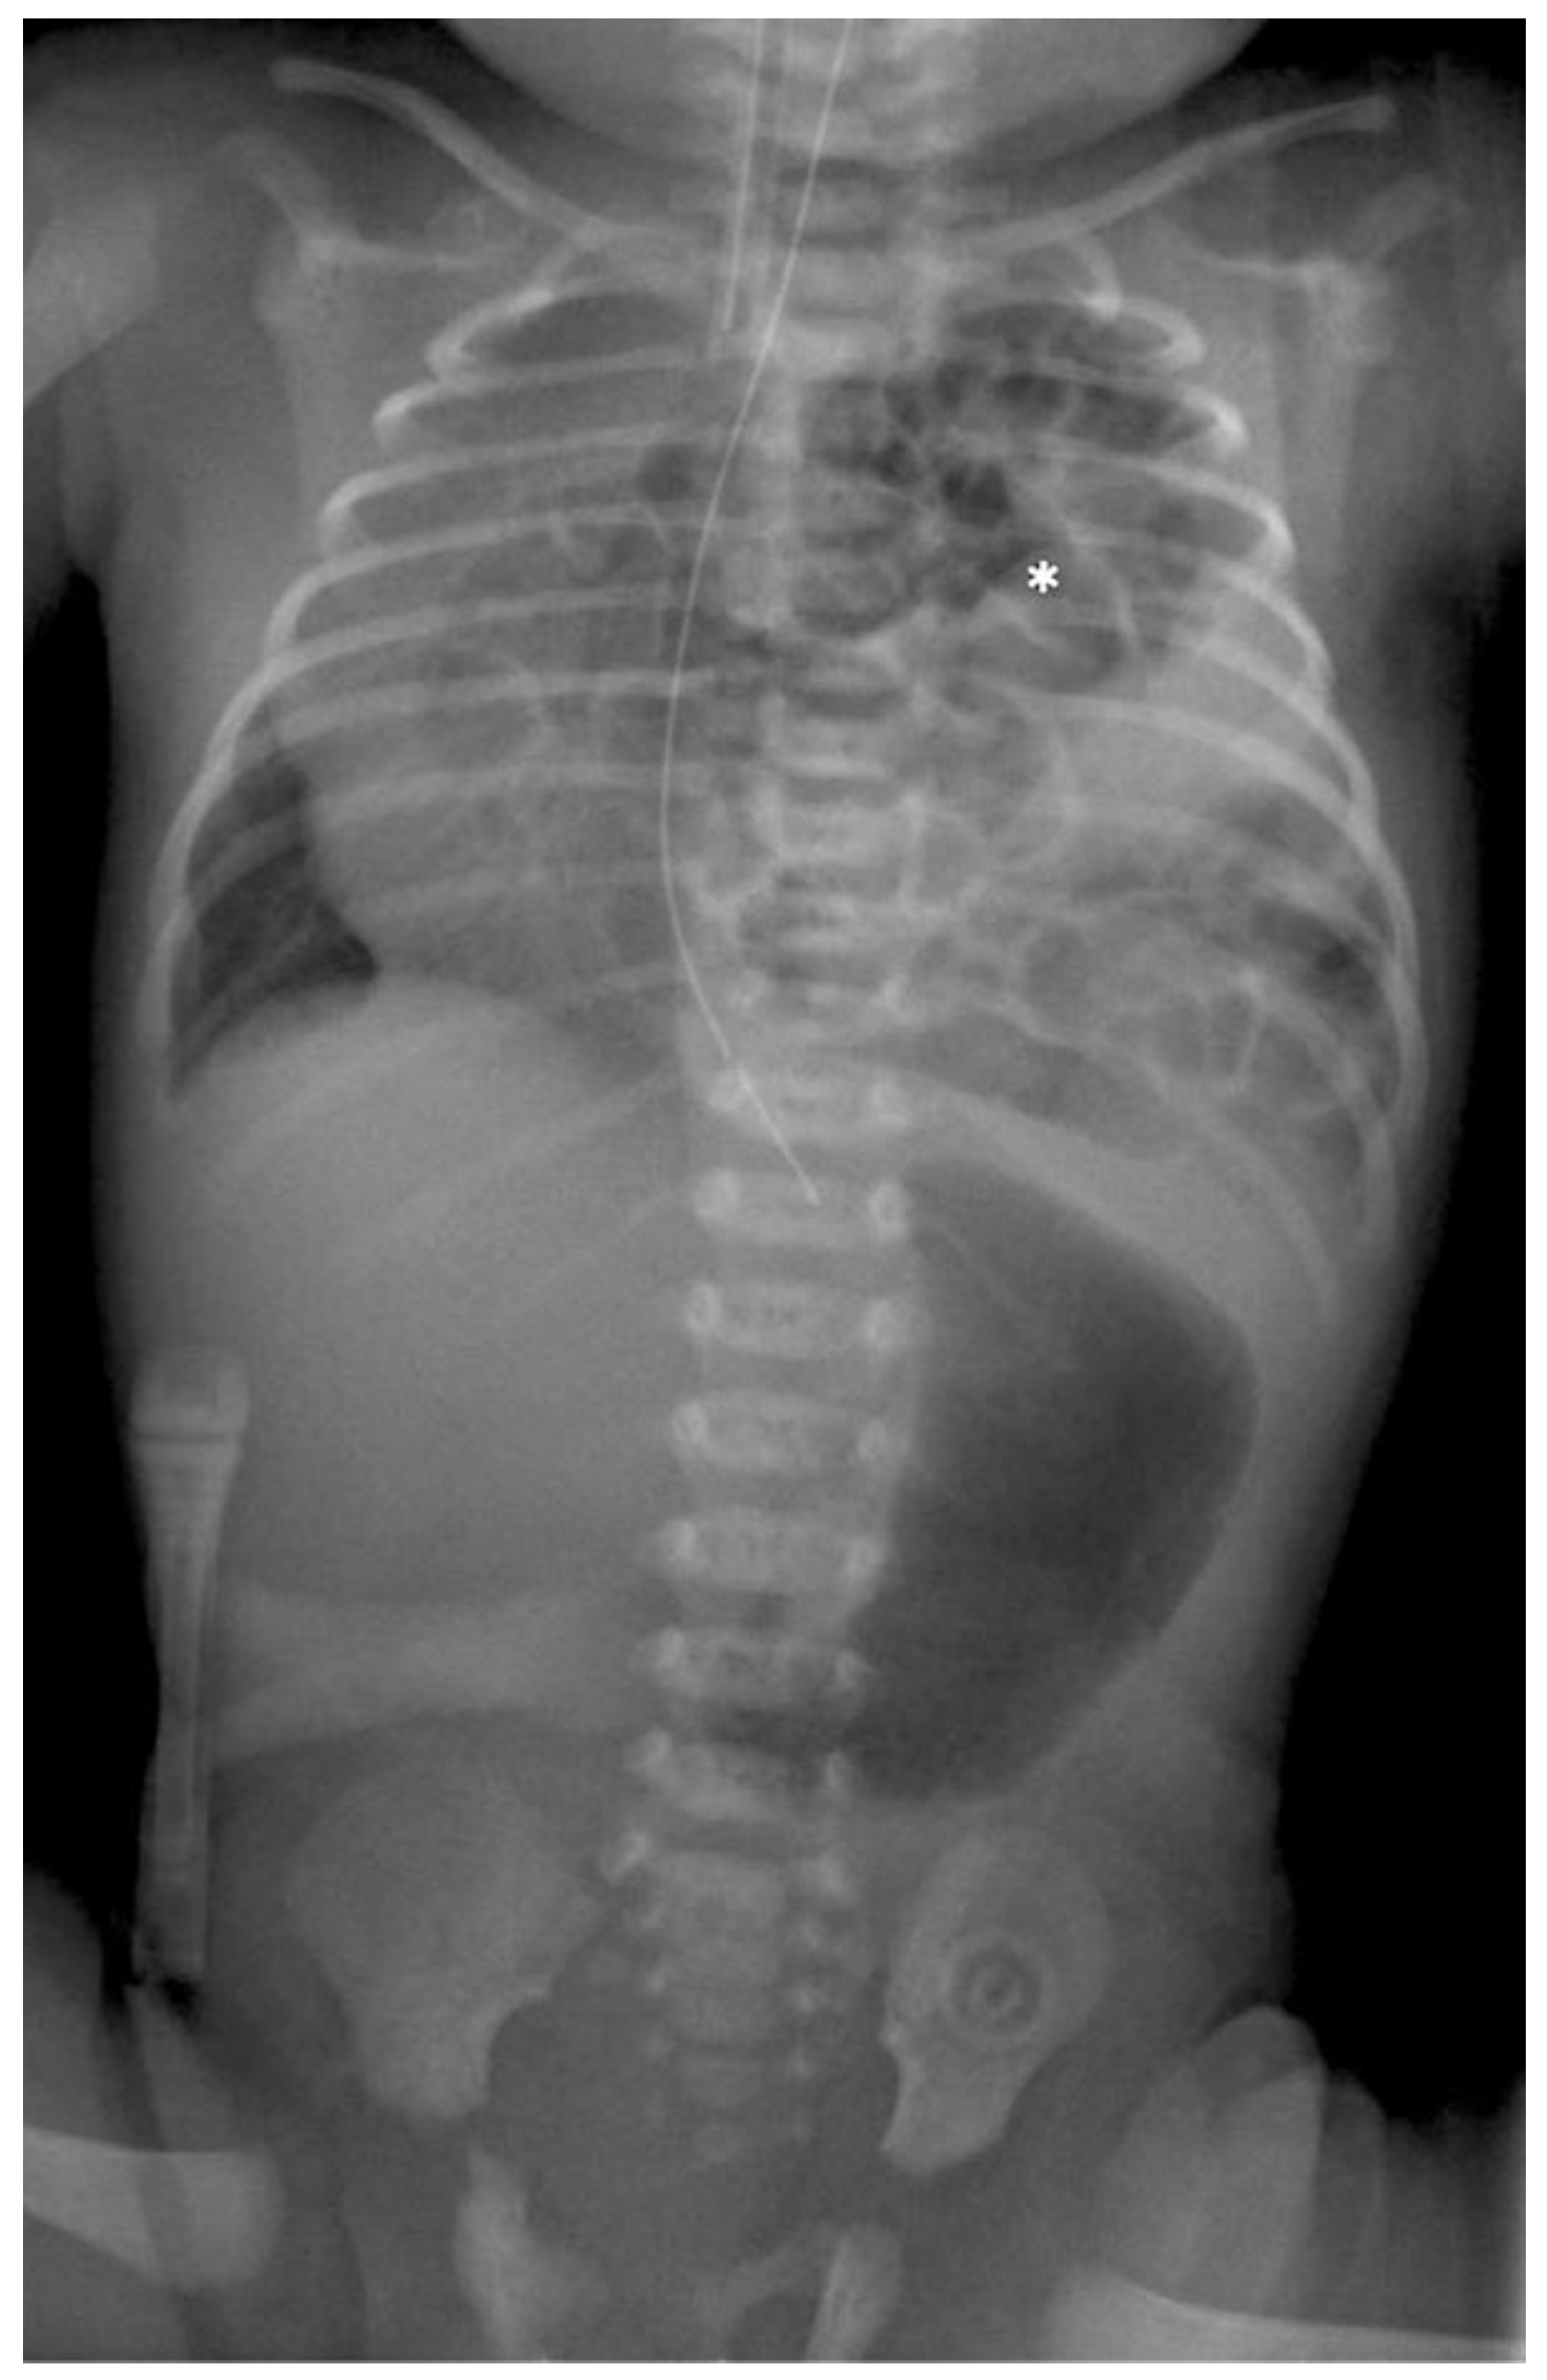

A control X-ray is taken on the ICU 2–4 h after the end of the operation (see Figure 6). All operations were conducted by the same surgeon.

Figure 6. The postoperative radiograph.